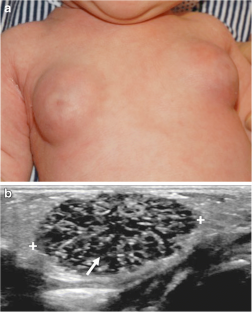

Jawahar A, Vade A (2014) Sonographic features of physiologic neonatal breast enlargement. J Clin Neonatol 3:106–108

Borders H, Mychaliska G, Gebarski KS (2009) Sonographic features of neonatal mastitis and breast abscess. Pediatr Radiol 39:955–958